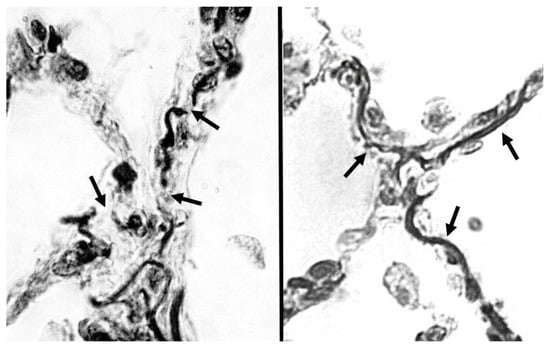

Beyond the Critical Threshold: Elastic Fiber Remodeling and Fracture in the Pathogenesis of Pulmonary Emphysema

Pulmonary emphysema is a progressive and debilitating lung disease characterized by the destruction of alveolar walls and enlargement of airspaces, resulting in impaired gas exchange and reduced lung function. Central to this pathology is the degradation of the extracellular matrix (ECM), particularly the [...] Read more.

Pulmonary emphysema is a progressive and debilitating lung disease characterized by the destruction of alveolar walls and enlargement of airspaces, resulting in impaired gas exchange and reduced lung function. Central to this pathology is the degradation of the extracellular matrix (ECM), particularly the elastic fiber network containing elastin protein responsible for storing and releasing the energy that expels air from the lung. Both intrinsic and extrinsic mechanical stress play a pivotal role in ECM remodeling, influencing elastin degradation and the structural integrity of alveolar walls. This paper explores the interactions between mechanical forces and ECM components, emphasizing the role of increased elastin crosslinking in the pathogenesis and progression of emphysema. The molecular mechanisms responsible for this process are described in the context of emergent phenomena associated with alveolar wall distension and rupture, including the role of diagnostic biomarkers in the early detection of elastic fiber injury that may facilitate timely therapeutic interventions designed to preserve ECM integrity and improve patient outcomes. Full article

Show Figures

Figure 1